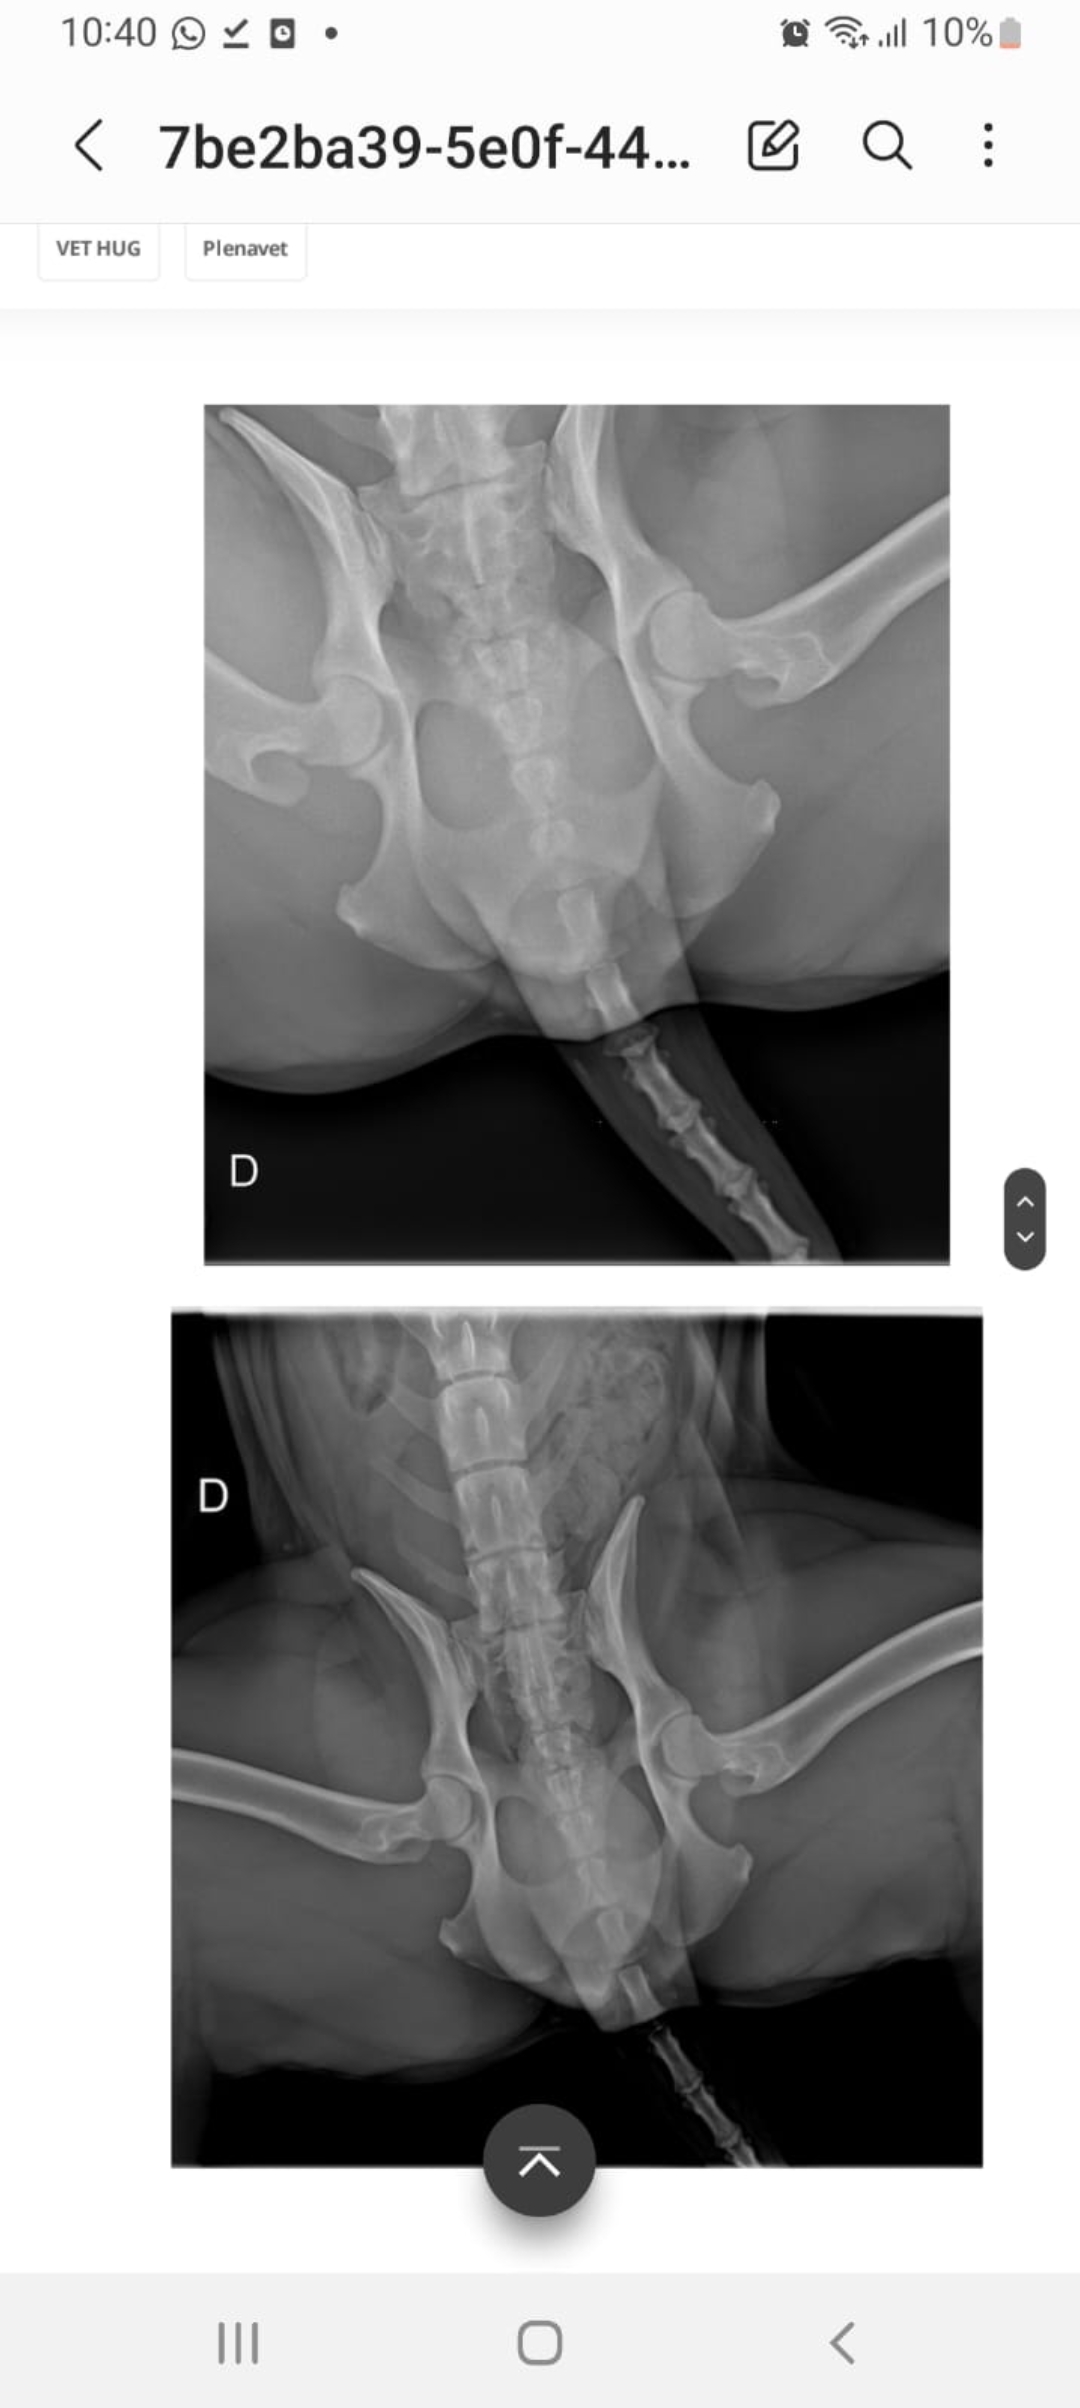

Raio X